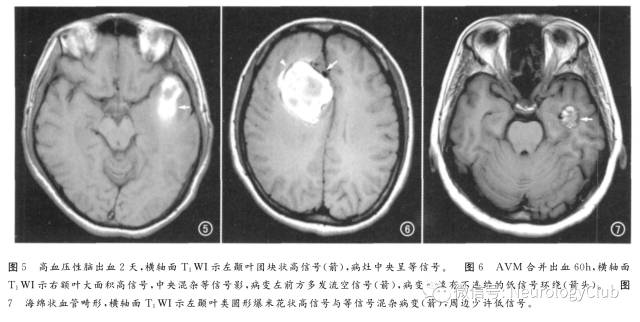

自发性脑实质内血肿病因包括高血压、淀粉样变、动脉瘤及血管畸形破裂、生发基质出血和血液系统疾病等,以高血压性脑出血最常见,好发于基底节、丘脑和内囊,而淀粉样变和血管畸形的出血易见于脑叶或皮层下。血肿信号变化复杂,取决于病程、大小、部位、血红蛋白的氧合状态、血凝块收缩程度、灶周水肿及患者血色素水平等。脑内血肿演变分为5期:①超急性期,细胞内氧合血红蛋白;②急性期,氧合血红蛋白向脱氧血红蛋白演变;③亚急性早期,细胞内高铁血红蛋白;④亚急性晚期,红细胞崩解,产生细胞外高铁血红蛋白;⑤慢性期,巨噬细胞将血红蛋白转变为含铁血黄素及铁蛋白。不同部位及大小的血肿演变有差异。典型的自发性脑内血肿信号变化自周边向中心扩展,出血后第1周,血肿内铁为二价氧化为三价,具有显著超顺磁性,T1WI上呈高信号(图5),这种高信号呈向心性扩展;亚急性晚期(第1-2周),高铁血红蛋白进入细胞外,血肿于T1WI、T2WI上均为高信号。

特殊原因的脑内血肿:①淀粉样变所致的脑内血肿可较大,也可较小,后者在常规T1WI上难以显示,而在T2*WI及SWI上为多发斑点状低信号,富有一定特征性;②脑血管畸形,包括发育性静脉畸形、动静脉畸形(图6)、毛细血管扩张症、海绵状血管畸形(图7)。其中动静脉畸形约占脑内出血的2%;海绵状血管畸形常有慢性隐性出血,MRI为其首选影像学检查,典型表现为爆米花状高信号及病变周围含铁血黄素所致的信号环,但SWI比T1WI对出血更敏感。